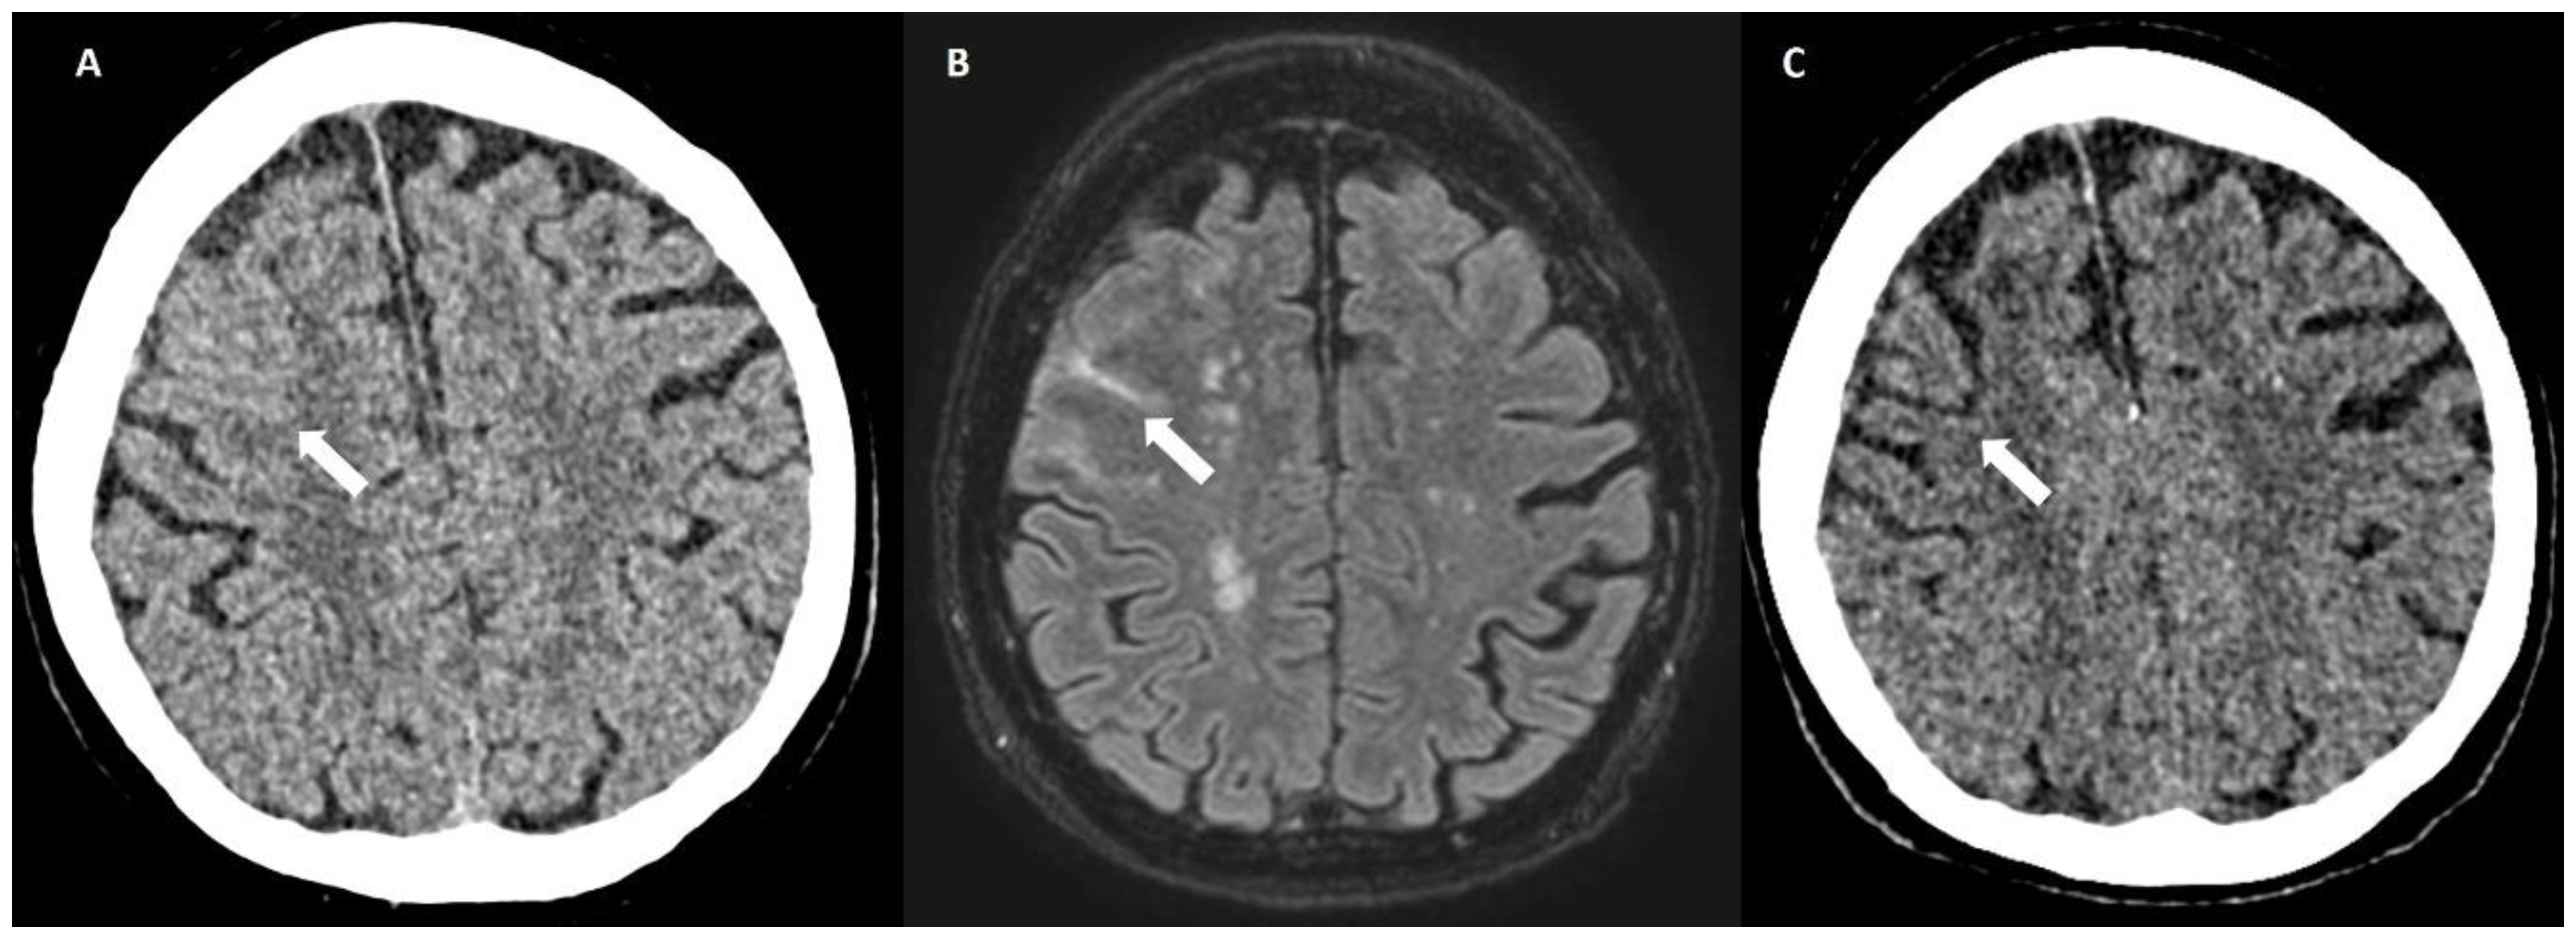

5.1.2. Multiple Cerebral Microbleeds

5.2.1. Enlarged Perivascular Spaces

6.3. DWI Lesions

6.4. Lobar Lacunes